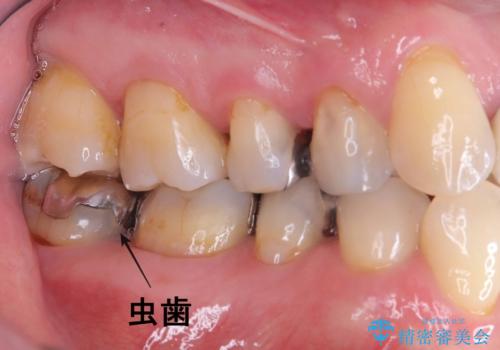

【オールセラミッククラウン】銀歯の下が虫歯に!

- 当院にメインテナンスで通っていただいている患者様です。銀歯の下の虫歯が大きくなってきたので、治療を行いました。

銀歯を外し虫歯を除去後、オールセラミッククラウンで治療を行いました。

銀歯は錆びる金属が使用されており、型取りの材料も変形がある材料になってしまうので、再び虫歯になってしまっている患者さんが沢山おられます。